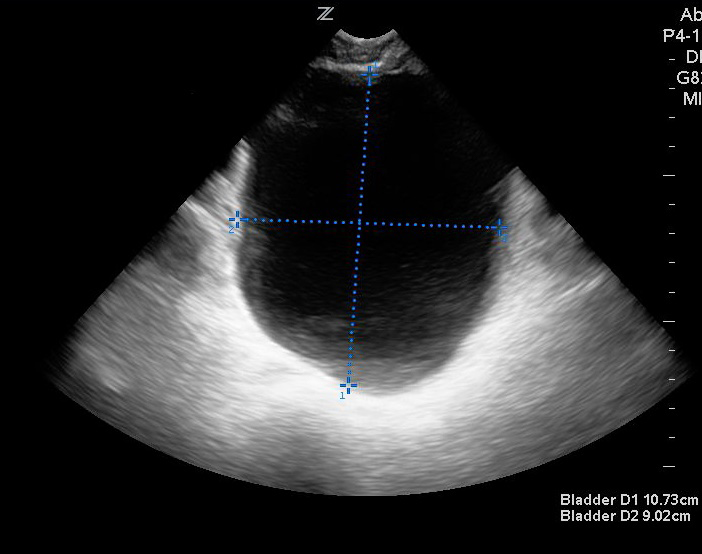

- Figures 3 and 4. Measurement of bladder volume in the transverse (Figure 3) and sagittal (Figure 4) views

- For measuring bladder volume, use the US volume measurement feature or the formula 0.52 × Depth × Width × Height.

- In the transverse view, find the largest bladder size and measure both the vertical and horizontal length of the bladder image from inner wall to inner wall. This corresponds to the bladder depth and width, respectively.

- In the sagittal plane, measure the maximum horizontal length of the bladder image from inner wall to inner wall. This corresponds to the bladder height.